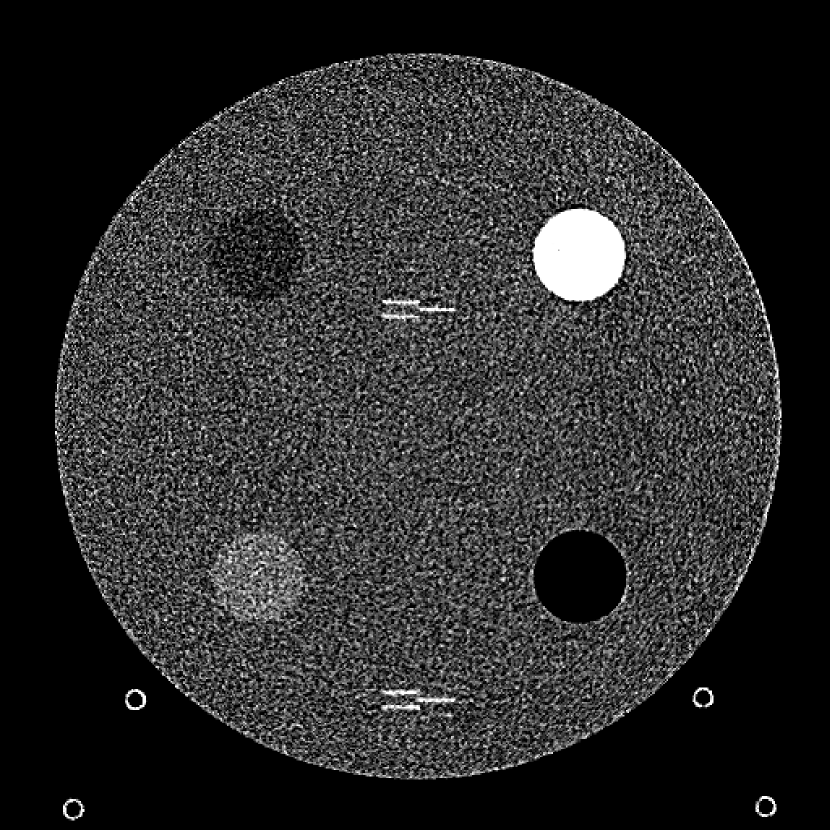

Figure 9: (a) The ACR phantom module 1 with 4 different inserts for CT number fidelity testing. In addition, two ramps of wires are visible near the phantom center. The image display window center is 150 HU and window width is 700 HU. (b) The phantom module 3 with a uniform water-equivalent radiodensity of 0 HU. The display window center is 0 HU and window width is 400 HU.

To evaluate image quality, we first tested the performance of JENG on a standard CT phantom, CT ACR 464 phantom 35. Then we tested JENG on 5 clinical thoracic datasets and 3 abdominal datasets. The ACR 464 phantom contains four modules in total, with each module 40 mm in depth and 200 mm in diameter. The first module has 4 different inserts to test CT number fidelity. In addition, the module contains a series of wires for cross-plane resolution evaluation, shown as white horizontal bars near the center in Fig. 9(a), and are visible in 0.5 mm z-axis increments. The second module tests low contrast resolution, but is not used in this paper. The third module, shown in Fig. 9(b), is a uniform cylinder of water-equivalent material of 0 Hounsfield units (HU), and we used this module to quantitatively measure image noise profile and in-plane resolution. The fourth module consists of resolution bars of various spatial frequencies for analysis on high contrast resolution. To scan the phantom, the scanner setup used dual sources with 2 focal spots at each source. In addition, the projections were acquired using the same protocol for clinical thoracic scans with 100 KV, a nominal tube current of 718 mA and a high helical pitch of 2.8. For all experiments, we compared JENG against the state-of-the-art Siemens ADMIRE, reconstructed with a BL-64 soft tissue sharp kernel, and we define ADMIRE as the clinical standard hybrid IR method for the rest of the paper.

The first experiment we performed was a visual comparison of in-plane spatial resolution between JENG and the clinical standard hybrid IR. We used the ACR phantom module 4 for this evaluation, which has 8 resolution bars of various spatial frequencies from 0.4 mm-1 to 1.2 mm-1. To obtain a fair comparison, we matched the image noise variance in the uniform regions of JENG and the clinical standard hybrid IR and studied their in-plane spatial resolution and undersampling streaking artifacts. In addition, we performed two sets of experiments. The first set of experiments matched their image noise variance at the L1 denoising strength of the clinical standard method with a noise variance of 33926 in the uniform regions. The second set of experiments matched their image noise variance at stronger L3 denoising strength of the clinical standard method with a noise variance of 12988 in the uniform regions.

The resolution bar visual comparison study, however, can be biased by observer subjectivity and may provide little information for spatial resolution beyond a limiting value. Therefore, we also quantitatively evaluated the Task-Based Modulation Transfer Function (MTFtask) of JENG and the clinical standard hybrid IR for a more complete analysis on in-plane resolution, using the edge of the uniform water-equivalent material phantom in module 3 as shown in Fig. 9(b). In summary, our MTFtask analysis was measured with the water-equivalent phantom and averaged all transaxial images in module 3 into a 2D image. Then the MTFtask analysis computed the oversampled edge-spread-function for the generated 2D image, differentiated and Fourier transformed the edge-spread-function to the frequency domain 38, 3. The MTFtask is then the absolute value of the Fourier Transform result and the source code of our MTFtask computations can be downloaded from citation 39.

For a more complete image analysis, we also measured the Noise Power Spectrum (NPS) and we visually compared the cross-plane spatial resolution of JENG and the clinical standard hybrid IR. The NPS computations followed the same procedures as in citation 38 with source code from citation 39. In summary, we selected multiple regions of interest in module 3 and all regions were squares of the same size and had an average radiodensity of 0 HU. In addition, neighboring regions of interest overlapped with each other. Then, we performed a Fourier Transform on each region of interest and the final NPS value equals to the ensemble average of the squared Fourier Transform. For cross-plane resolution qualitative evaluation, we visually compared the wire pattern image sharpness between the two algorithms for the series of wires of module 1 from sagittal view. For qualitative evaluations, we reconstructed JENG with a resolution no worse than the clinical standard hybrid IR and compared image noise and artifacts between the two algorithms.